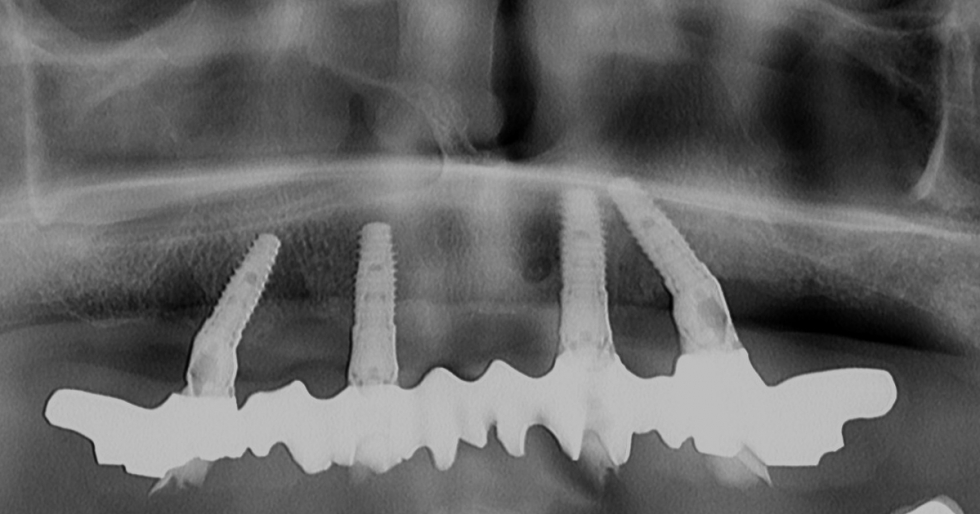

TORNARE A SORRIDERE con gli impianti e senza usare il bisturi

Oggi è possibile tornare a sorridere con i denti anche per chi ormai li ha persi da tempo o li sta perdendo. La tecnica di  ALL ON FOUR permette di inserire impianti e mettere un carico immediato, cioè fissare i denti sugli impianti e tornare a mangiare il giorno stesso dell'intervento.  inoltre è possibile eliminare il bisturi perchè la tecnica utilizzata ci permette spesso di progettare il posizionamento degli impianti senza l'uso del bisturi e con poche e semplici manovre si mettoni 4/6 impianti senza dover tagliare la gengiva come veniva fatto in passato

RX del caso iniziale che mostra distruzione ossea e tasche parodontali infette

RX panoramica dopo l'estrazione dei denti che mostra lacune ossee

TAC che mostra l'aspetto tridimensionale dell'osso

RX con la simulazione degli impianti prima del loro inserimento

si applica una mascherina di resina che serve da guida per l'inserimento degli impianti senza usare alcun tipo di bisturi

gli impianti appena inseriti. Come si può vedere non c'è sangue, né tagli visibili

rx finale con i denti montati sugli impianti

i denti fissati in modo stabile immediatamente alla fine dell'intervento